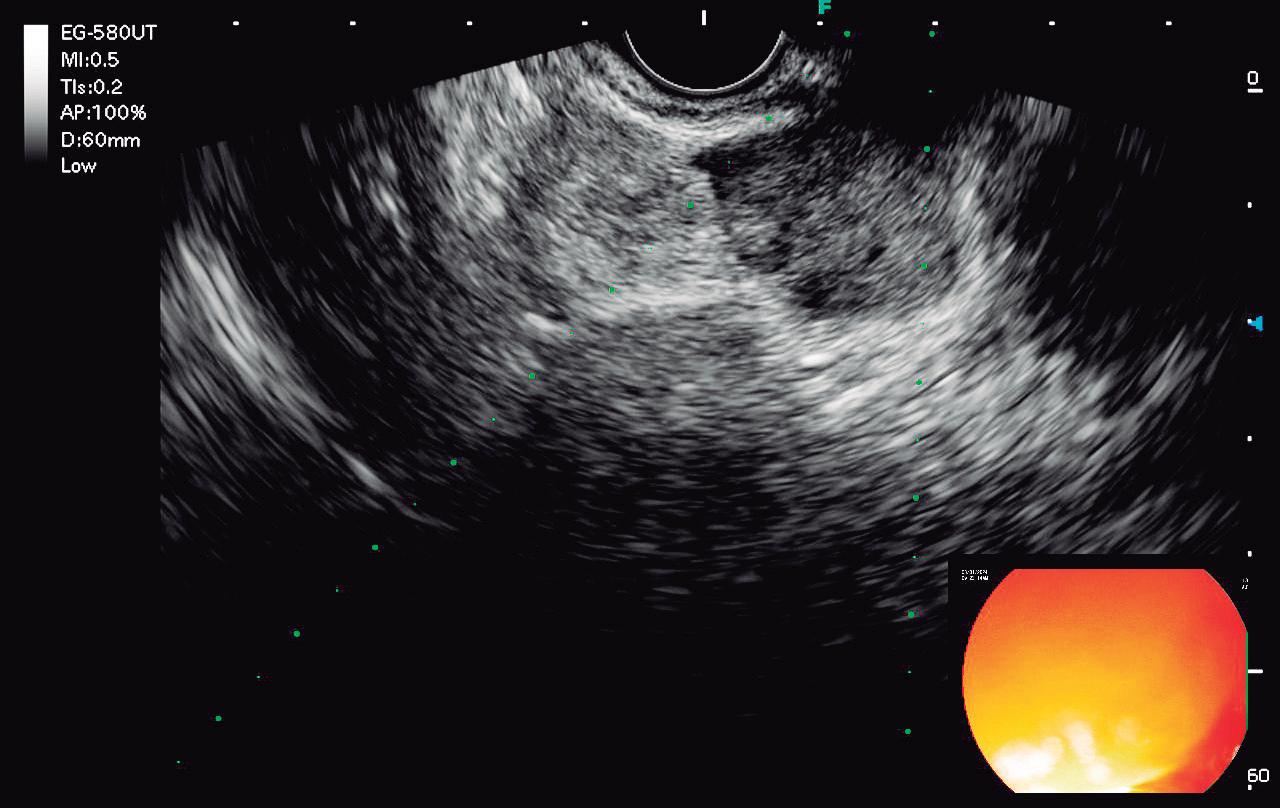

CASOS CLÍNICOS Biopsia guiada por ecoendoscopía como herramienta diagnóstica mínimamente invasiva para metástasis mesorrectal de carcinoma de células claras renales: reporte de caso

Nicole Marie Kahn, Mayra Florencia Defanti, Yanina Gabriela Carlino

CASE REPORTS Endoscopic Ultrasound-Guided Biopsy as a Minimally Invasive Diagnostic Tool for Mesorectal Metastasis From Clear Cell Renal Carcinoma: A Case Report